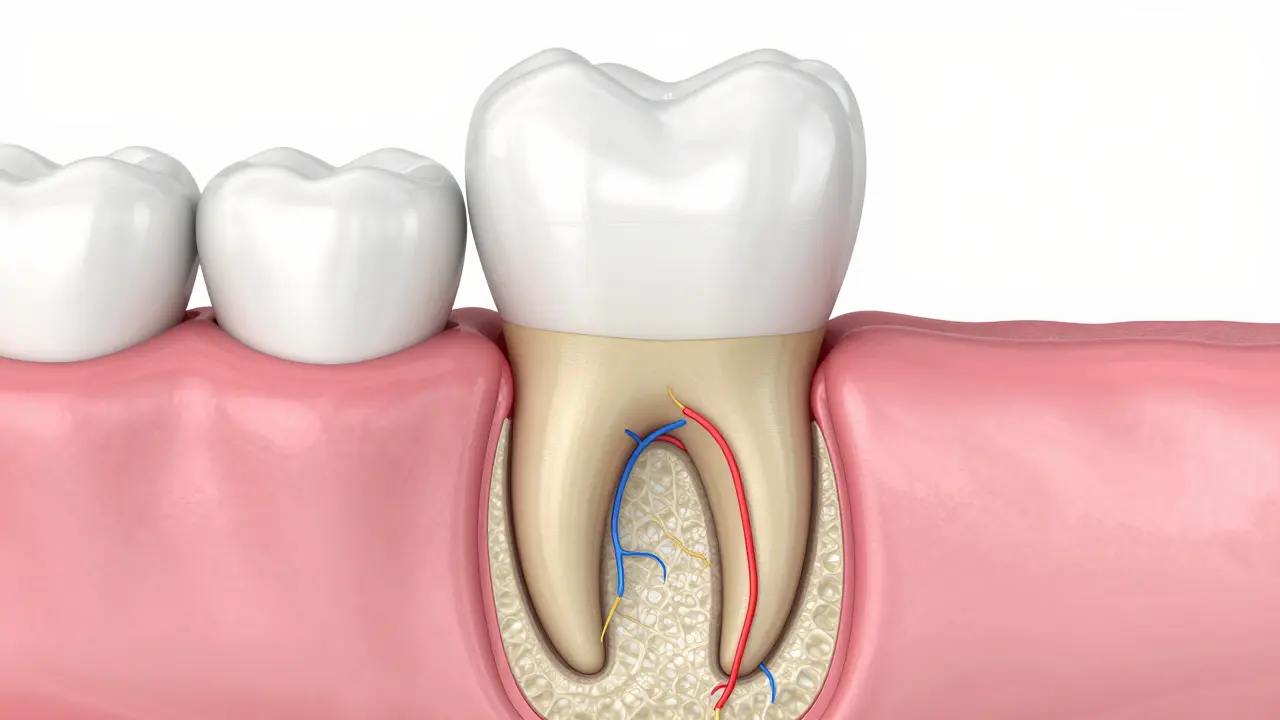

Když se podíváme pod dásně, zjistíme, že kořen není jen "hřebík" v kostě. Je to komplexní struktura. Nejvnější vrstvou je cement je tenká vrstva kostní tkáně, která pokrývá povrch kořene a pomáhá mu připojit se k periodontu. Na rozdíl od skloviny, která je nejtvrdší tkání v těle, je cement mnohem měkčí a náchylnější k odлізу.

Uvnitř kořene běží tzv. dentin je hlavní tvořivá tkáň zubu, která tvoří jádro jak korunky, tak kořene. Je to v podstatě vyztužený "beton", který chrání nejcitlivější část zubu.

V úplném centru najdeme zubní pulpu je měkká tkáň obsahující nervová zakončení, krevní cévy a zvazky, která vyživuje zub. Když vám zub "bolí", většinou jde o zánět právě v této části, která v kořeni končí úzkým otvorem zvaným foramen apicale.